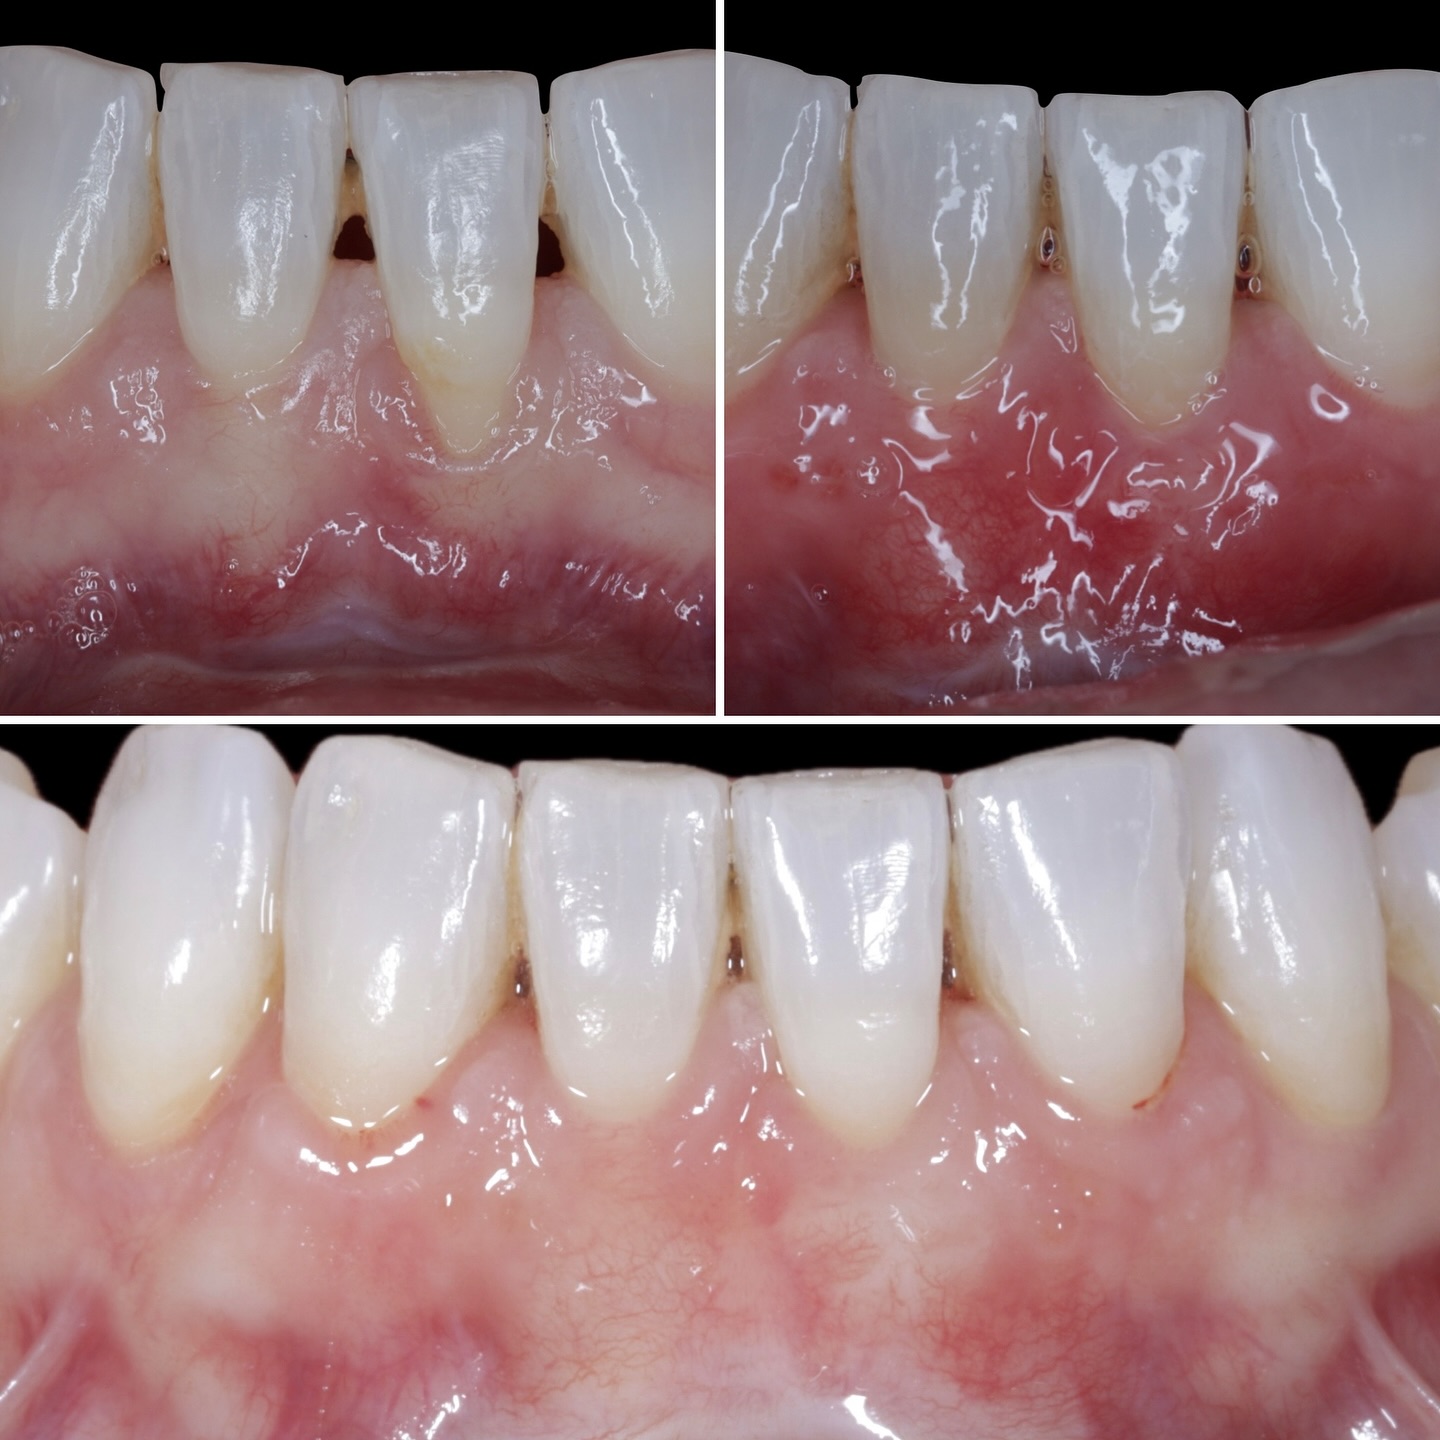

Se presenta un caso clínico de restauración directa en resina composite, ejemplo del valor de la precisión y la técnica meticulosa incluso en procedimientos considerados rutinarios dentro de la práctica diaria. El caso pone en evidencia la importancia del control de la morfología, la textura y la integración cromática, así como del adecuado aislamiento del campo operatorio y la estratificación del material, factores determinantes para conseguir un resultado natural, funcional y duradero. A través de una ejecución cuidadosa, se logró una restauración estéticamente imperceptible y funcionalmente estable, que respeta los principios de mínima invasión y adhesión efectiva. Este tipo de procedimientos, aunque cotidianos, reflejan la constancia y el nivel de exigencia clínica necesarios para ofrecer odontología de calidad en todos los casos, independientemente de su complejidad.

Durante una mañana, asistirás a una Cirugía Mucogingival de recubrimiento radicular de recesiones múltiples en IV y V sextante (36 a 43).

Gracias al uso del microscopio y a la proyección en tiempo real en pantalla, verás exactamente lo mismo que veo yo durante la cirugía, sin tener que estar

Aprende la planificación y técnica de la cirugía Mucogingival para el recubrimiento de recesiones y aumento de banda queratinizada en el sector anteroinferior

Durante una mañana, asistirás a una Cirugía Mucogingival de recubrimiento radicular de una recesión unitaria en 31 con frenillo asociado. Gracias al uso del microscopio y a la proyección en tiempo real en pantalla, verás exactamente lo mismo que veo yo durante la cirugía, sin tener que estar